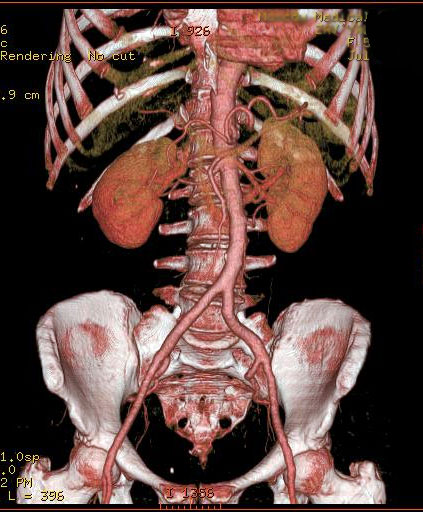

Объемный сбор данных и высокая скорость получения срезов при МСКТ значительно расширили области использования КТ [11, 12]. Так, КТ-ангиография стала распространенным методом визуализации практически всех сосудов, особенно коронарных [2]. Появилась возможность за одно исследование получить изображение всего сосудистого русла человеческого тела (Рис.1).